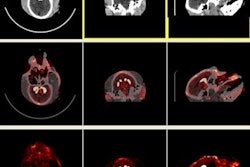

Researchers have found autoencoders to be useful in other instances as well, such as in developing algorithms for diagnosing autism on resting-state functional MRI and classifying Alzheimer's disease and mild cognitive impairment using MRI and PET data, according to Chang.